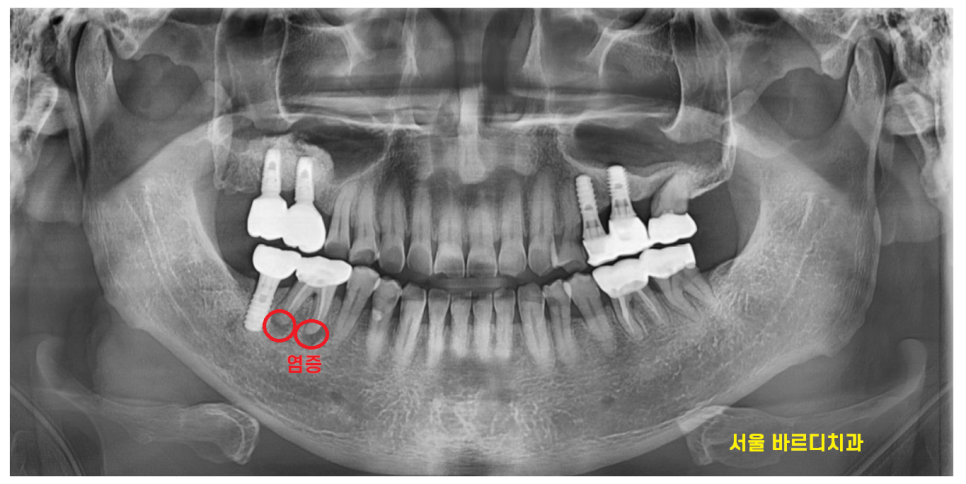

24.03.29

내원하셨을 때는

잇몸 풍선 터져서 오셨는데요.

여전히 고름이 나오고

좋지 않은 상황이었습니다.

신경치료도 되어있고

뼈도 많이 녹아있어서

발치 후 미사역 임플란트 하기로

상담해드렸습니다.